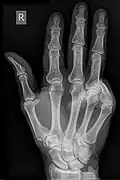

X-rays done to further understand the deformity.

Imaging Examinations

Imaging can help further determine features of the deformity.[24] Features observed depend on the deformity of concern. For example, specific damage can possibly be visualised for certain acute trauma deformities [14]